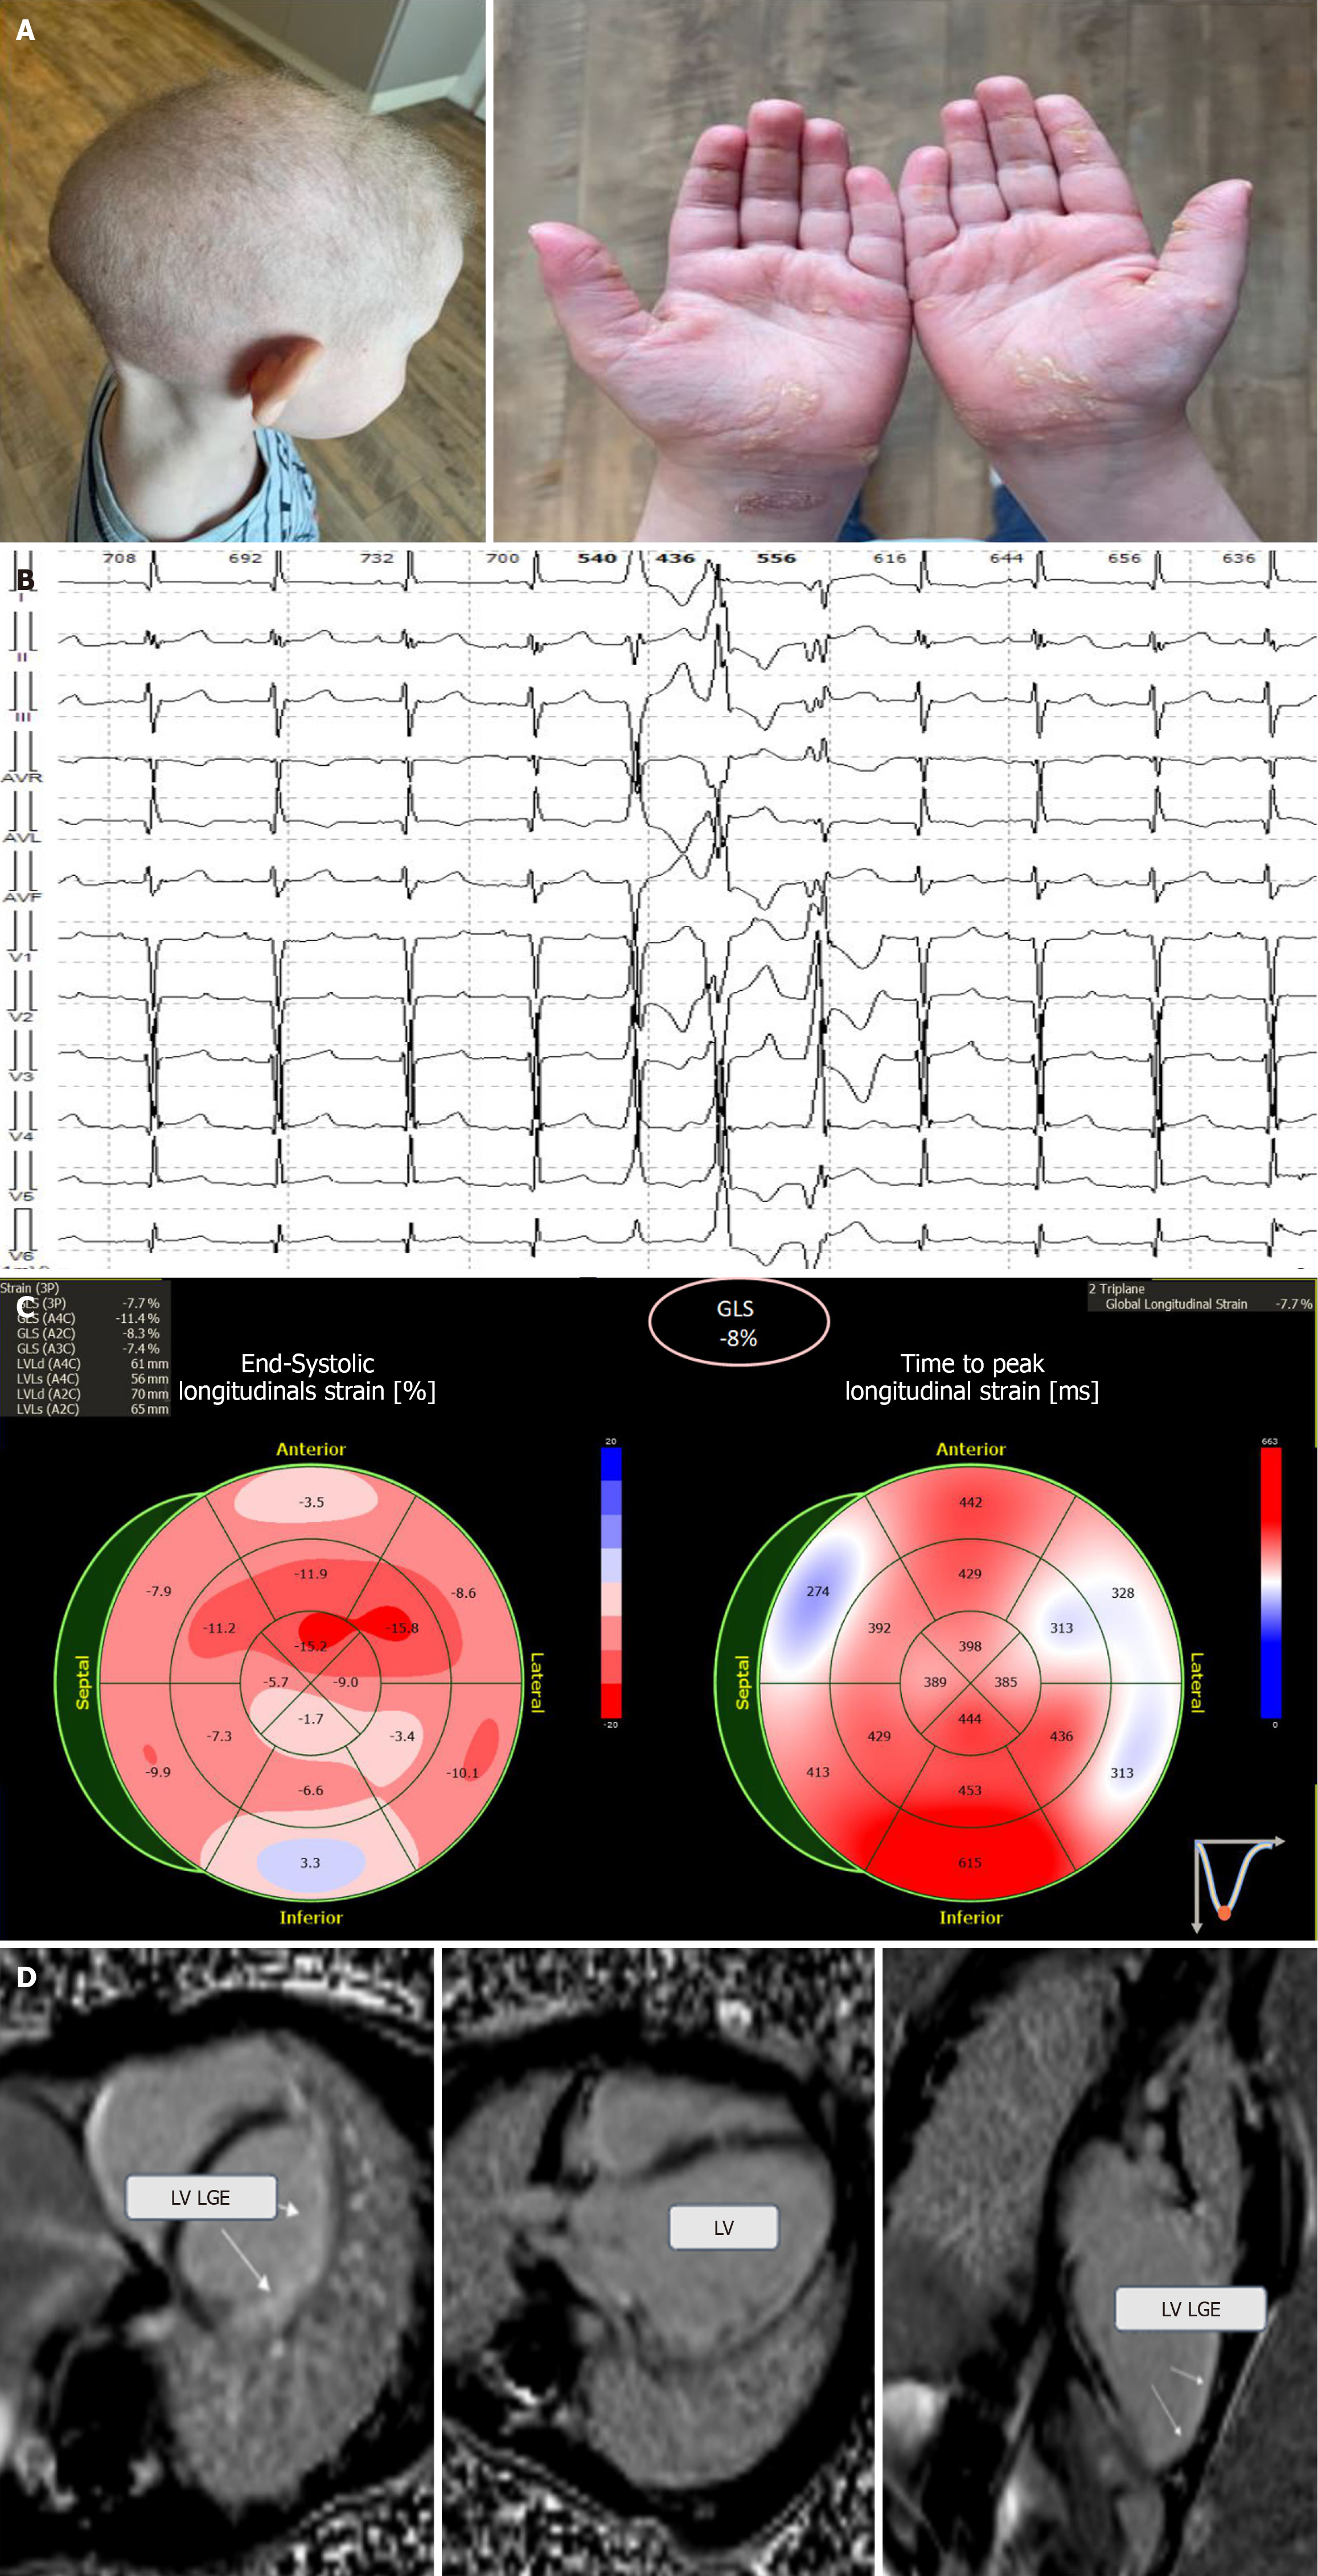

Figure 2 Phenotypic characteristics, electrocardiography, echocardiography, and cardiac magnetic resonance imaging of a 4-year-old child with Carvajal syndrome.

A: Child’s phenotypic characteristics: Curly-wool hair and palmoplantar keratoderma; B: Electrocardiography (ECG) fragment with polymorphic ventricular tachycardia and a heart rate ranging from 128 to 165 per minute; C: Echocardiography: Global longitudinal strain decreased by 8% due to hypokinesis in the left ventricular (LV) posterolateral segment; D: Cardiac magnetic resonance imaging: LV dilation and late gadolinium enhancement in the ventricular myocardium. RA: Right atrial; RV: Right ventricular; LGE: Late gadolinium enhancement.